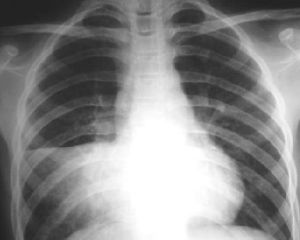

胸腔內臟器官疾患需藉助有關的器械檢查確定診斷如心電圖檢查有助於心絞痛和急性心肌梗死的診斷超聲心動圖對心包積液的診斷及觀察積液量有重要意義肯定瓣膜病診斷胸部X線檢查在現代胸部疾患的診斷占有重要地位常規X線檢查可顯示計多胸部病變的影像作為病變的診斷依據如肺炎肺結核肺梗死肺癌胸膜病變氣胸等CT檢查具有很高的解析度診斷準備性和敏感性甚高CT是橫斷面顯示胸部斷面圖像對縱隔旁橫膈周圍及胸膜下病灶的顯示效果良好常能區別血管脂肪水及各種軟組織密度的病變;常用於縱隔病變肺門增大的鑑別肺內微小病灶及胸膜病變MRI檢查具有能冠狀面和矢狀面斷層成像並對縱隔內軟組織分辯率更高等優點能直接維甚至任意角度斜切面成像更有利於病變的顯示和定位;但CTMRI檢查在胸部病變不宜作為首選只能作為進步檢查的辦法放射性核素掃描對肺梗死肺內占位病變心肌梗死的診斷有幫助心導管檢查對於先天性和某些後天性心血管疾病診斷有特別價值對肺部疾病的診斷亦有意義纖維支氣管鏡可深入到面和亞段支氣管可在直視下做活檢和刷檢做活組織病理檢查支氣管肺泡灌洗液作微生物學細胞學免疫學分子生物學檢查對肺疾病的病因和病理診斷很有幫助胸腔鏡檢查用於胸膜疾病的診斷氣胸的分類及冶療

1.胸壁病變胸壁變所引起的胸痛是各類胸痛中最常見的一種,如胸壁的外傷,細菌感染,病毒感染,腫瘤等引起的局部皮膚,肌肉,骨骼及神經病變。常見的急性皮炎,皮下蜂窩組炎,帶狀皰疹,痛性肥胖症,肌炎及皮肌炎,流行性肌痛,頸椎痛,肋軟骨炎,骨腫瘤,肋間神經炎,神經根痛等。其中共同特徵:1.疼痛的部位固定於病變處,且局部有明顯壓痛。2.深呼吸、咳嗽、舉臂、彎腰等動作使胸廓活動疼痛加劇。2.肺及胸膜病變肺和髒層胸膜對疼痛覺不敏感,肺炎,肺結核,肺膿腫,肺梗死等,由於病變累及壁層而發生胸痛。肺癌侵及支氣管壁及壁層胸膜都可產生胸痛。自發性氣胸時由於粘連撕裂產生突然劇痛。乾性胸膜炎由於炎症波及髒層和壁層胸膜發生摩擦而致胸痛。大量胸腔積認與張力性氣胸可由於壁層胸膜受壓發生胸痛。其共同特點為:1.多伴咳嗽或咳痰。2.常因咳嗽、深呼吸而胸痛加重,其他胸壁活動並不引起疼痛,3.胸壁局部無壓痛。常伴有原發疾病之症征,X線檢查可發現病變。